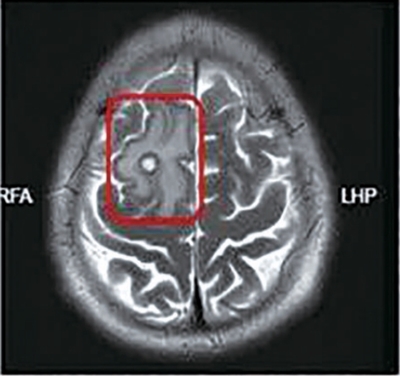

2025年8月20日   2026年3月6日   经过半年治疗,患者颅内病灶水肿逐渐吸收缩小。

去年8月,小王再次发病,住进了树兰(杭州)医院感染病科病房,高海女主任带领的诊疗团队没有局限于初步的影像学判断,而是结合患者既往发病史、检查结果与饮食暴露史,逐一排除肿瘤、脑血管病变等其他病因,最终考虑寄生虫感染可能。详细问诊中,小王坦言发病前半年春节回老家曾吃过生猪血。

复盘整个病程,患者既往有生食猪血史,与脑内额叶寄生虫病灶、癫痫发作的症状高度吻合,彻底揭开了这场突发疾病的谜底。最终明确诊断:脑囊虫病。

经过系统性、针对性的规范治疗后,患者颅内病灶水肿逐渐吸收,出现缩小趋势。近日小王和妻子来杭州进行半年复查:颅内病灶较半年前明显缩小,身体抽搐症状消失。